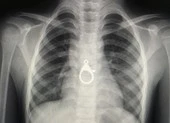

Ảnh: Bệnh viện cung cấp.

Tiếp đó, bệnh nhân được chỉ định nội soi kiểm tra thực quản và can thiệp đặt Stent kim loại thực quản có bao phủ kết hợp dẫn lưu và tưới rửa khoang màng phổi trái.